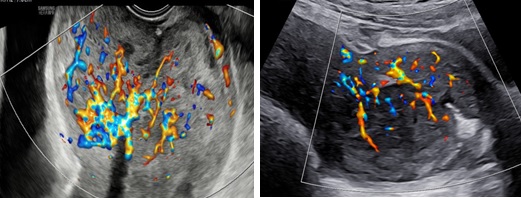

Siêu âm: Tử cung ngã trước, kích thước: 56 x 62 x 90 mm. Cơ tử cung mật độ đều, đồng nhất. Từ thành trước đoạn thân nhô vào lòng tử cung kéo dài tới cổ tử cung có khối echo dày không đồng nhất kích thước 64 x 81 x 70 mm, không rõ ranh giới với cổ tử cung và cơ tử cung. Trên Doppler màu khối tổn thương phần ở lòng tăng sinh mạch máu độ 2 và ở vùng cổ tử cung độ 4.

Hình 1: Hình siêu âm 2D ngã bụng (trái) và ngã âm đạo (phải) cho thấy tổn thương từ lòng tử cung lan tới cổ tử cung, không thấy ranh giới của khối này với cơ vùng cổ tử cung

Hình 2: Trên Doppler màu, khối trong lòng tử cung tăng sinh mạch máu mức độ 2

Hình 3: (trái: ngã âm đạo, phải: ngã bụng): Trên Dopple màu, phần tổn thương ở cổ tăng sinh mạch máu độ 4, không ranh giới giữa tổn thương và cơ vùng cổ tử cung